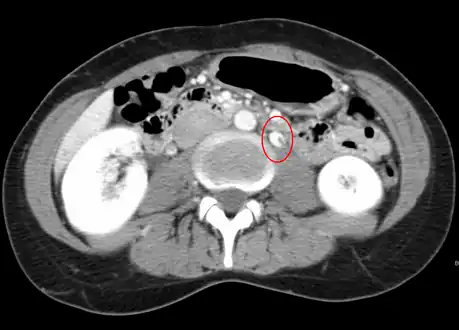

CT showing dilatation and thrombosis of the left renal vein in a patient with nutcracker syndrome

Observing the patient's symptoms, medical history and imaging remain the fundamental source for diagnosing RVT. Imaging is used to detect the presence of a blood clot. In an abnormal kidney with RVT, a blood clot is present in the renal vein. In cases where the renal vein is suddenly and/or fully blocked, the kidneys will enlarge, reaching its maximum size within a week. An ultrasound imaging can be used to observe and track the size of the kidneys in RVT patients. Ultrasound is not efficient for use in detecting blood flow in the renal veins and artery. Instead a color doppler ultrasound may be used to detect renal blood flow. It is most commonly used to detect RVT in patients who have undergone renal transplantation. CT angiography is currently the top choice in diagnosing RVT. It is non-invasive, relatively cheap and fast with high accuracy. CT scanning can be used to detect renal enlargement, renal tumors, blood flow and other renal pathologies. An alternative is magnetic resonance angiography or MRA. It is non-invasive, fast and avoids radiation (unlike a CT scan) but it is relatively expensive. MRA produces detailed images of the renal blood flow, vesicle walls, the kidneys and any surrounding tissue. An inferior venocavography with selective venography can be used to rule out the diagnoses of RVT.[6]